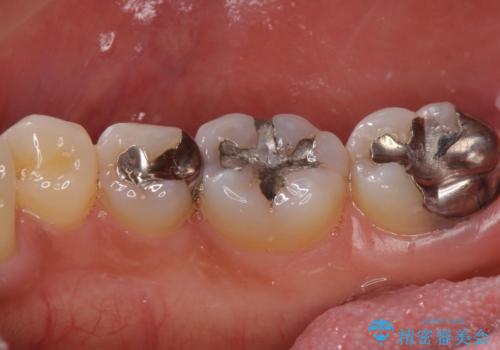

- 右下奥歯が気になるとのことで来院された患者様です。

銀の詰め物の適合が悪く、歯と銀歯の間に歯茎が入り込んできている状態でした。

銀歯を除去し、適合の良いゴールドアンレーで修復していきます。